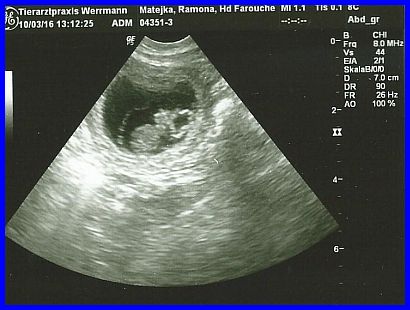

Auch hier wieder sehr gut zu erkennen, ein schon relativ großer Welpe. Die Welpen sind hier 29 Tage alt!